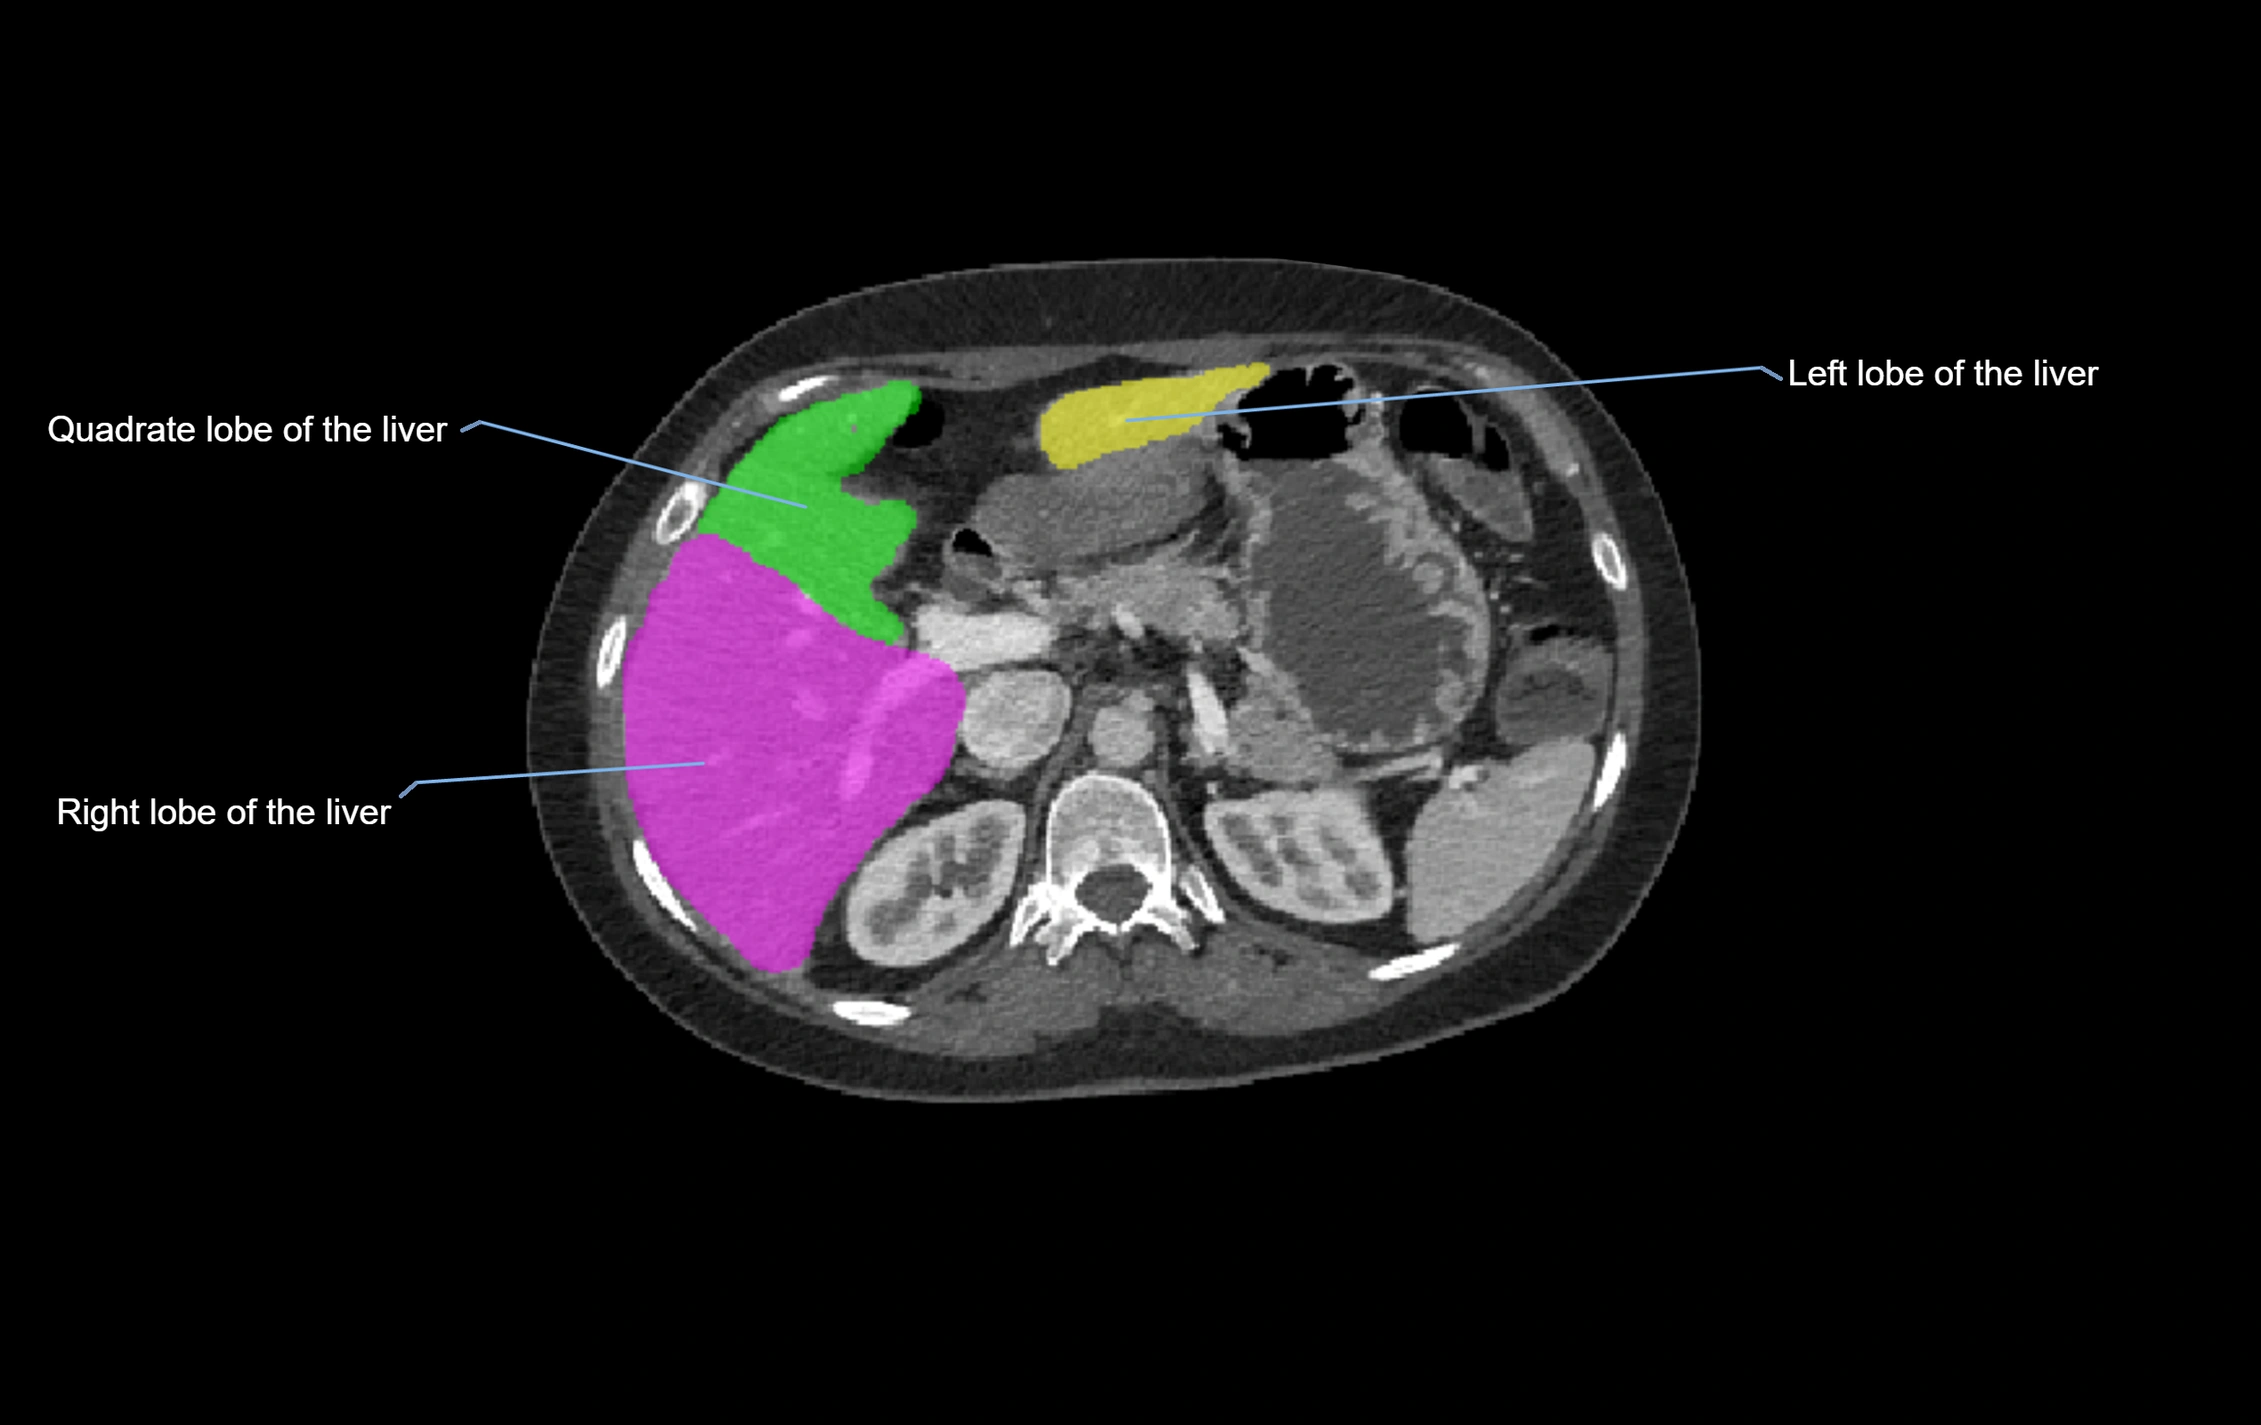

CT Image

image